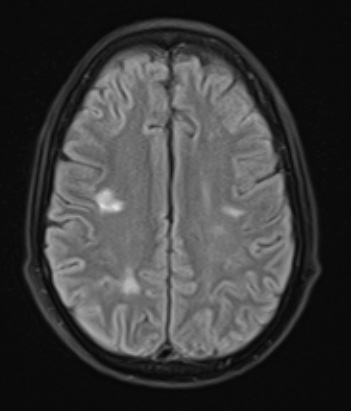

18A1,2 There are numerous hyperintense white matter lesions visible on this FLAIR (18A1) and T2-weighted without contrast (18A2) scans.